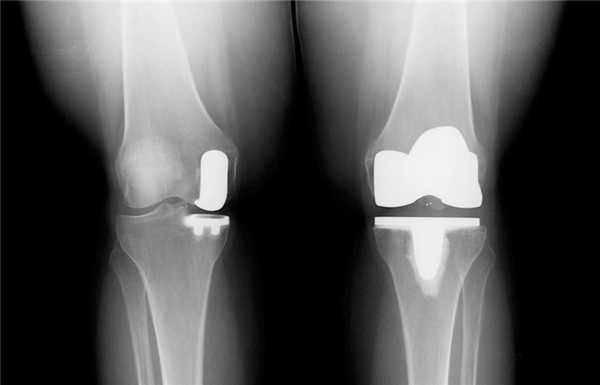

Результат частичной замены коленного сустава на рентгене.

- – сочленение меняется на имплантат только частично. Замене подлежит или наружный, или внутренний бедренно-большеберцовый компонент. Такая тактика целесообразна лишь при условии, что структуры противоположной половины сустава, ПКС, ЗКС целые. Процедура малотравматичная, реабилитация после нее проходит относительно легко и быстро. – операция предполагает полное замещение всех суставных поверхностей на искусственные аналоги. Вмешательство делается при обширной деструкции хрящевой материи, диагностируемой одновременно и в медиальном, и латеральном отделах.

Частичный и тотальный способ.